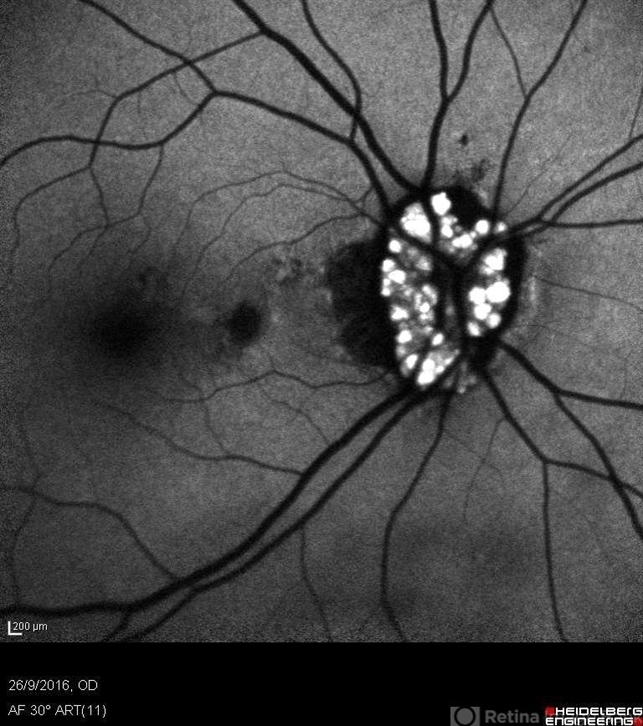

- drusen of optic disc, calcified drusen

Heidelberg - HRA Angiograph, Autofluorescence com 30 degrees. - Description

- Female patient, 37 years old, Caucasian, with complaint of low lateral stroke in abos the eyes. In the retinal mapping examination and retinography, important alterations in the optic nerve head suggestive of DRUSAS DE PAPILA were observed. After being confirmed in the Autofluorescence examination, we observed Autohyperfluorescence compatible with deposits of calcified hyaline material, as well as another complementary exam such as USG and OCT.